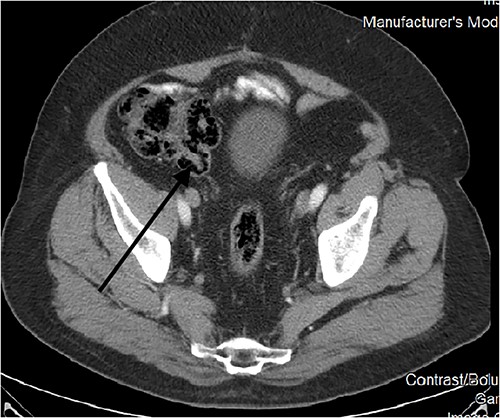

CT scans also picked up this anomaly as early as 2010 (Fig. 2). Further scans in the following years showed no change in morphology (Fig. 3a and b), and it was kept under surveillance. To note, our patient did not have any abdominal symptoms suggestive of appendiceal origin throughout the years.

Endoscopically, it appears as a tubular elongated polypoid structure arising from the appendiceal orifice [11, 12]. Endoscopists can be reluctant to rule out neoplastic findings without a histological confirmation (such was the case in our patient’s 2012 colonoscopy). On CT scans, it appears as an elongated structure with a layered appearance at the appendiceal orifice. The presence of feces in the cecum might make diagnosis difficult [13].

Appendiceal intussusception is classified according to the McSwain classification: Type 1: tip of the appendix invaginates into the appendiceal lumen. Type 2: extension of type 1 where there is more pronounced invagination beyond the tip of the appendix. Type 3: the appendix intussuscepts all the way to the appendiceal orifice at the caecum, which is the most common type. Type 4: retrograde inversion of the proximal appendix distally toward the tip. Type 5: complete invagination of the appendix through the orifice into the cecum [13]. Our case is classified as Type V.